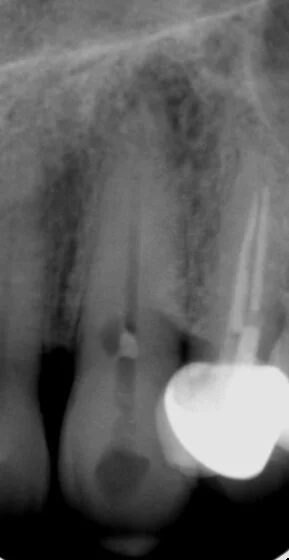

This young man was referred to me for root canal retreatment of the lower right first molar tooth as his dentist had planned to crown the tooth as it had an extensive filling in it. An x-ray of the tooth revealed that there was evidence of a piece of fractured instrument in one of the root canals and the root canal treatment was not ideal. As would be the standard of care, the referring dentist wished to try and optimise the root canal treatment before crowning the tooth. This gentleman was seen and the tooth was accessed. A small fragment of an instrument was retrieved from the canal and the root canal treatment was subsequently completed without complication, allowing this gentleman to have a crown placed and retain the tooth. As is often the case trying to retain ones own tooth is best.